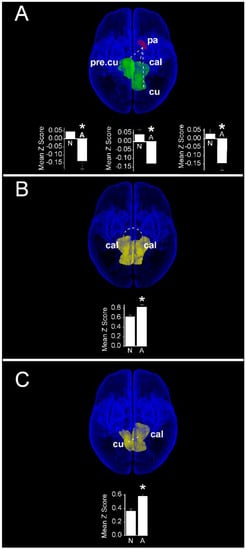

In contrast to cognitive scores, increased functional connectivity in infants with normal motor scores compared with those having abnormal motor scores were restricted to interactions between the left pallidum and vision-related cortical regions (Figure 8A). Compared with children with abnormal motor scores, infants with normal motor scores demonstrated a greater functional connectivity between the left pallidum and each of the right precuneus (Normal: 0.05 ± 0.03 vs. Abnormal: −0.14 ± 0.05; PFDR = 0.015), left cuneus (Normal: 0.03 ± 0.03 vs. Abnormal: −0.14 ± 0.04; PFDR = 0.015), and left calcarine cortex (Normal: 0.04 ± 0.03 vs Abnormal: −0.13 ± 0.04; PFDR = 0.018). Notably, these infants also demonstrated a weaker functional connectivity compared with children having abnormal motor scores between bilateral primary visual (calcarine) cortices (Normal: 0.62 ± 0.03 vs. Abnormal: 0.83 ± 0.05; PFDR = 0.018, Figure 8B), as well as between the left calcarine and the contralateral cuneus cortex (Normal: 0.36 ± 0.03 vs. Abnormal: 0.59 ± 0.05; PFDR = 0.018, Figure 8C). Finally, we observed no significant differences in functional connectivity when infants with normal and abnormal language scores were compared.

Figure 8. Region pairs exhibiting increased and decreased functional connectivities in infants with normal (≥85) and abnormal (<85) scores on the motor subscale of the Bayley III assessment at two years post-menstrual age. Obliquely projected 3D reconstructions of MRI images of cerebral grey matter and identified parcellated regions derived from a neonatal atlas. Dashed white lines depict connectivity relationships. Inset: Fisher-transformed Z-scores ± 1 SEM. (A) Increased connectivity between pallidum and visual cortex regions: left: left pallidum and contralateral precuneus; middle: Left pallidum and ipsilateral calcarine cortex; and right: Left pallidum and ipsilateral cuneus. (B) Decreased connectivity between bilateral calcarine cortices; (C) Decreased connectivity between left calcarine and right cuneus. N: Normal; A: Abnormal. * PFDR < 0.05.